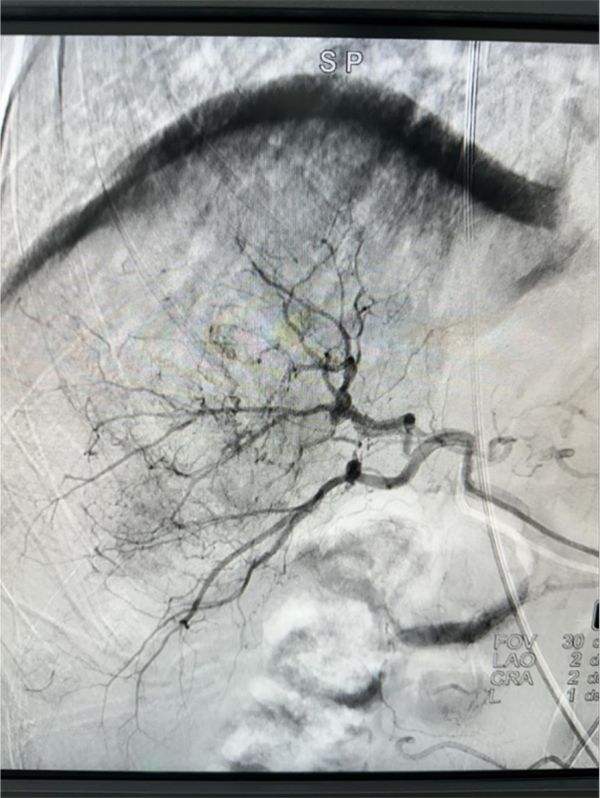

手术全程顺利,栓塞效果满意,有效控制肿瘤。肝癌是我国最常见的恶性肿瘤之一,早期症状一般不明显,等有症状再来医院就诊时,通常都是中晚期,大部分患者都失去了外科切除的机会,这个时候,介入治疗成为了控制肝癌的最常用手段。肝癌介入治疗(TACE)的核心原理,就是通过给肝癌提供营养的血管直接注入药物到癌细胞,然后堵塞营养血管,在杀灭癌细胞的同时,让癌细胞没有血流供应。

术前造影